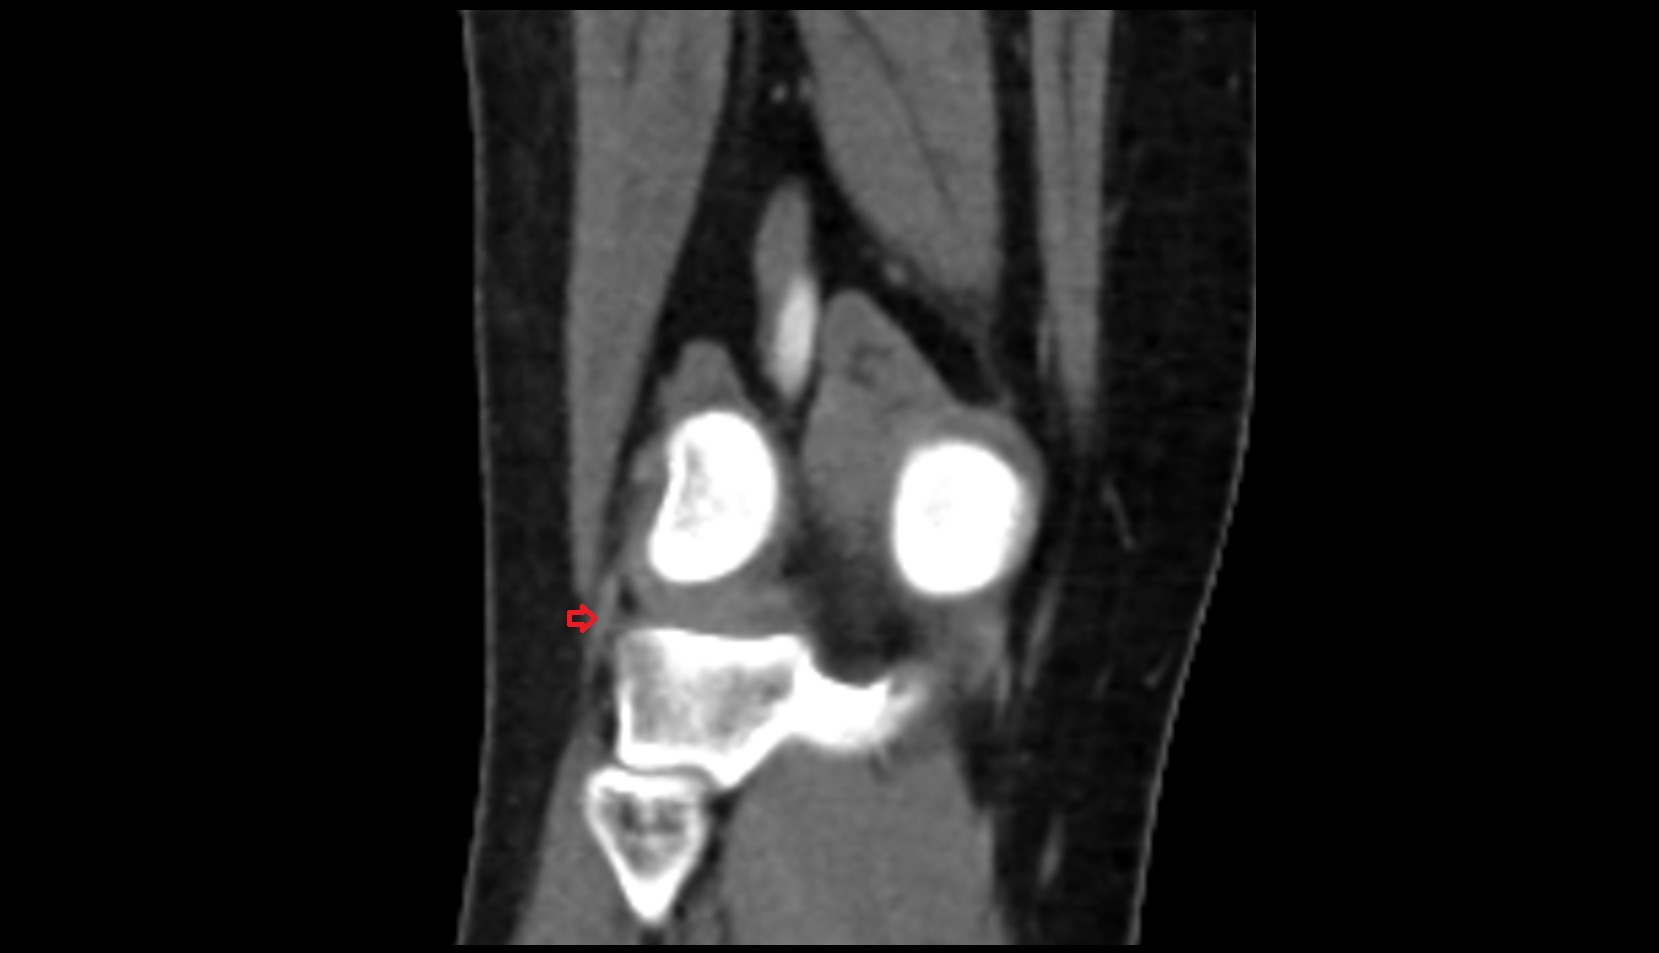

- Knee Joint